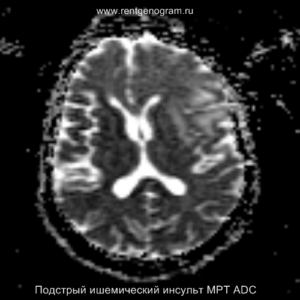

Острая фаза (6 — 24 часа)

В течение острого этапа на МРТ и КТ выявляются все морфологические признаки ишемического инсульта. Область острого ишемического инфаркта визуализируется как зона ↑Т2, ↑Flair, ↑DWI и ↓Т1 ↓ADC. Можно обнаружить тромб в артерии. На КТ в остром этапе также чётко дифференцируется поражённая область, представляющая собой участок с потерей дифференциации мозговых структур и снижением их плотности. Контрастирование в остром периоде не показывает патологических участков с накоплением контраста.

Когда в мозговых артериях происходит реканализация кровотока, это может привести к образованию геморрагических пропитываний и кровоизлияний («красный компонент» ишемического инфаркта), что будет отображаться на МРТ как ↑ на Т1 и Т2*, а на КТ — как участки с гетерогенной повышенной плотностью. На более поздних этапах подострой стадии наблюдается нормализация ранее повышенных показателей DWI и ADC, известная как «псевдонормализация» диффузии.